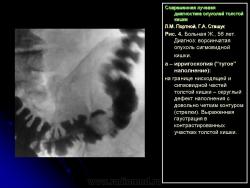

3. Симптом округлой (овальной) формы дефекта наполнения в просвете кишки:

– со всех сторон покрытый мелкими вкраплениями бариевой взвеси, что характеризует, как правило, ворсинчатую опухоль кишки (рис. 4);

Л.М. Портной, Г.А. Сташук